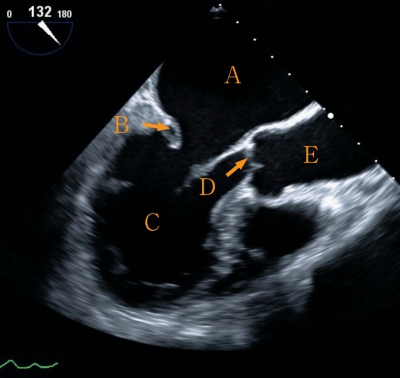

収縮期と拡張期の経食道心臓超音波像を別に示す。

正しいのはどれか。2つ選べ。

a. Aは右心房である。

b. Bは僧帽弁である。

c. Cは左心室である。

d. Dは肺動脈弁である。

e. Eは左心房である。